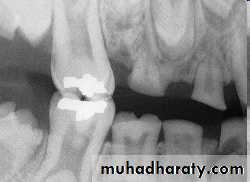

Paramolar blocking the eruption of 3rd molar.

MesiodensDistomolars(4th molar)

Distodens or distomolarParamolar